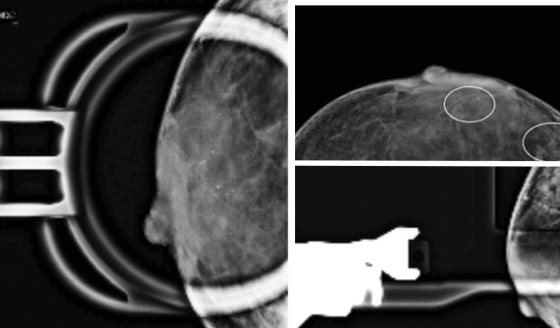

Se observaron fascias pálidas, mucosas secas, atrofia muscular en miembros inferiores y abdomen blando. Los estudios de imagen mostraron un tumor paraespinal derecho en mediastino posterior a nivel de las vértebras torácicas T8-T9, con calcificaciones y lesiones osteolíticas expansivas.

La resonancia magnética evidenció una masa de 9,9x10x9,4 cm con infiltración al canal medular y compromiso de la región posterior de la novena costilla.